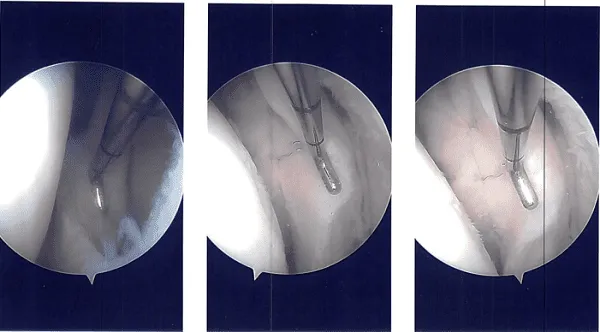

Se realizó cirugía artroscópica. Se realizó el portal anterior lateral para la observación artroscópica. Se introdujo el telescopio y se introdujo la cámara. La cámara mostró un desgarro del cuerno posterior y acercó el cuerpo posterior del menisco lateral alrededor del hiato poplíteo en su periferia.

El desgarro se podía reparar y decidí hacerlo. Había una lesión condral de grado 2 a grado 3 sobre la rótula así como el cóndilo lateral del fémur. Se realizó condroplastia. La raspa meniscal se utilizaba para preparar tanto la inserción capsular como la meniscal.

Se construyó un plano entre el poplíteo y el gastrocnemio con los recipientes detrás. El espéculo de Sims se utilizaba para retraer los vasos hacia atrás. Se reintrodujo otro endoscopio en el borde lateral y la reparación integral se realizó usando FasT-Fix con un implante curvo entero interno y suturas curvas Nephew.